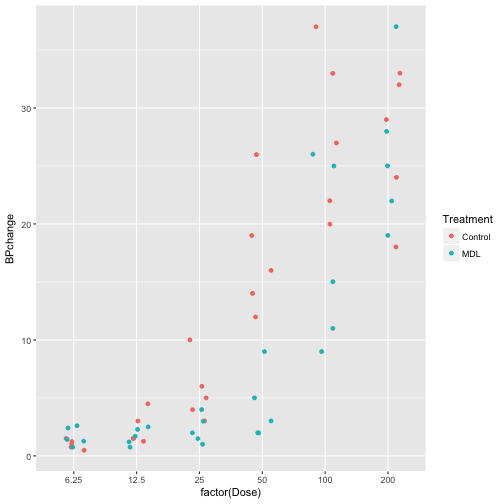

Stat_summary can be used to perform summary statistics in conjunction with various ggplot2 and hmisc functions.

For example, the mean_cl_normal function can be used to generate the mean and the lower and upper confidence limits on a variable.

# examine the Rabbit dataset

str(Rabbit)

## 'data.frame': 60 obs. of 5 variables:

## $ BPchange : num 0.5 4.5 10 26 37 32 1 1.25 4 12 ...

## $ Dose : num 6.25 12.5 25 50 100 200 6.25 12.5 25 50 ...

## $ Run : Factor w/ 10 levels "C1","C2","C3",..: 1 1 1 1 1 1 2 2 2 2 ...

## $ Treatment: Factor w/ 2 levels "Control","MDL": 1 1 1 1 1 1 1 1 1 1 ...

## $ Animal : Factor w/ 5 levels "R1","R2","R3",..: 1 1 1 1 1 1 2 2 2 2 ...

# create plot object BPchange vs. Dose using Rabbit dataset

p <- ggplot(Rabbit, aes(x = factor(Dose), y = BPchange, color = Treatment))

# take a look at the plot

p + geom_point(position = position_jitter(0.2))

# use stat_summary function to generate mean for each BPchange per Dose

p +

stat_summary(geom = 'point', fun.y = mean)